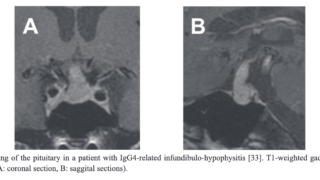

下垂体MRIでは明らかな異常が認められないため、原因不明の中枢性甲状腺機能低下症と診断されることが多い。しかし、造影MRIを行うと一部の患者では不均一な増強を伴うわずかに萎縮した下垂体前葉が認められる。